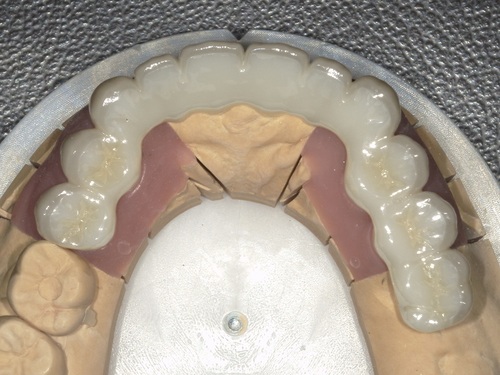

⑦セット

型取りから2週間ほどでジルコニアセラミックブリッジが完成してきました。

適合・色合い・噛み合わせに問題がないことを確認し、歯科用セメントでしっかりとセットしました。術前と比較して色も自然でとても美しい仕上がりかと思います。

ジルコニアセラミックとは「強度が必要な見えないフレーム部分をジルコニアという強度がある素材で作り』、『表面の見える部分にセラミックを貼り付けた』ジルコニアとセラミックを合わせた材料になります。メタルフリー(金属不使用)のため、金属アレルギーの心配がなく、強度と美しさを兼ね備えたとても素晴らしい材料になります。

また、表面がとてもツルツルしており、汚れが付着しにくく、ケアしやすい点も重要なメリットとなります。ブリッジは複数の歯が繋がっており、ケアが難しいです。ジルコニアセラミックを使えば決して虫歯や歯周病にならないという訳ではもちろんありませんが、ジルコニアやセラミックを用いることで、ブリッジなどのケアしにくい部位の虫歯や歯周病のリスクを下げることが可能です。